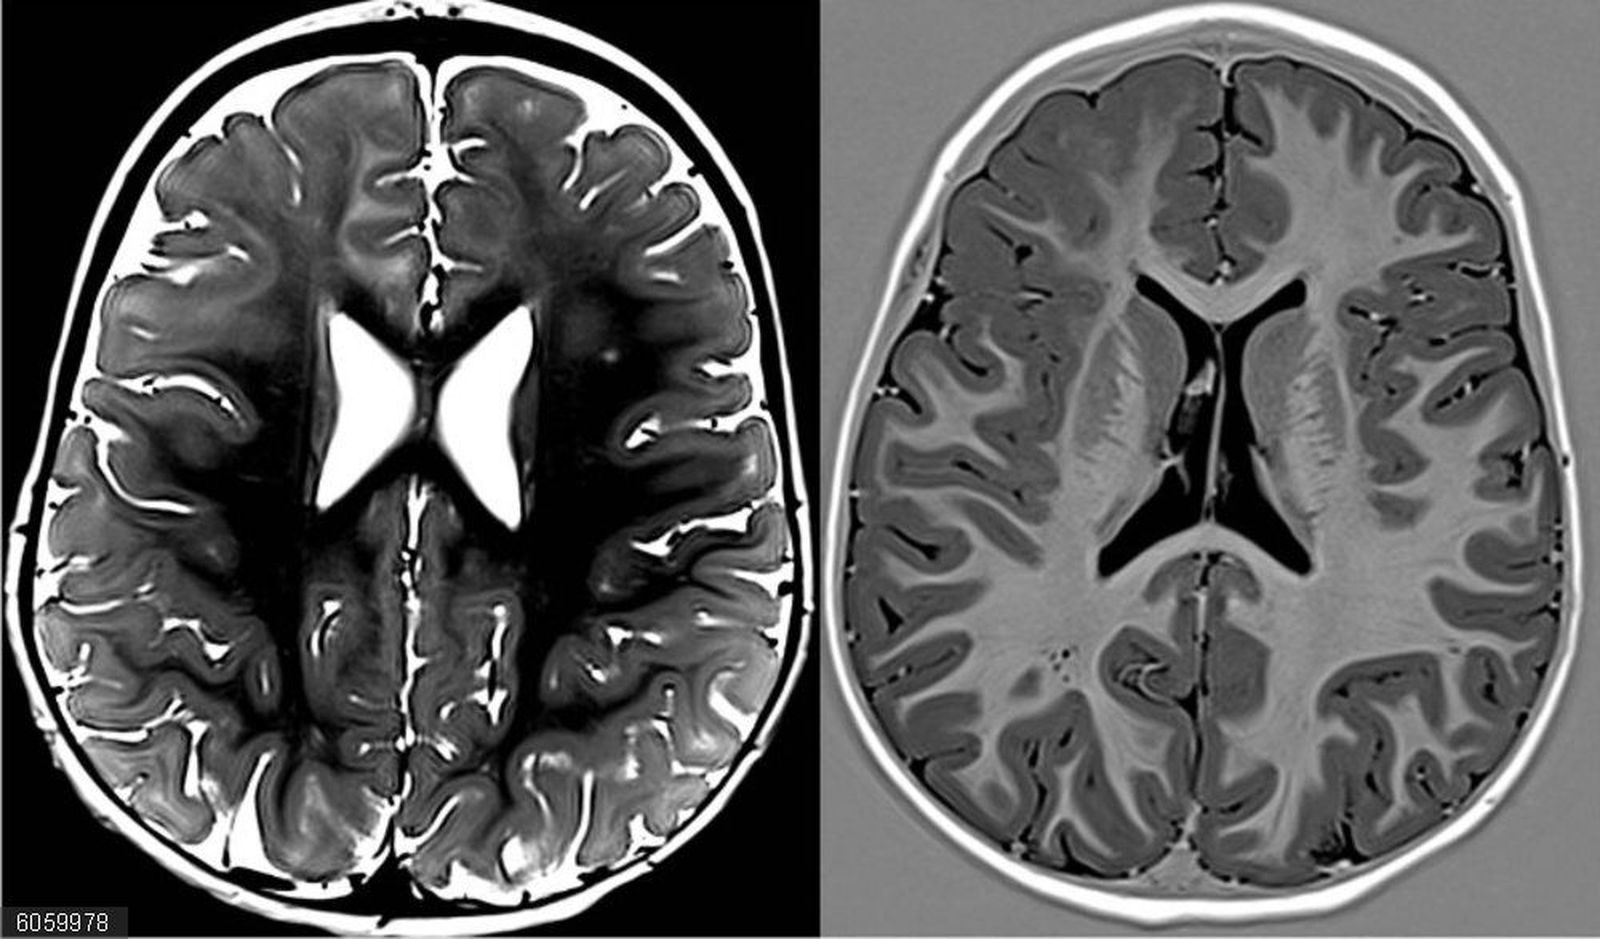

Ante la aparición de cualquier síntoma relacionado con la epilepsia, Rondón ha recomendado acudir a un centro médico para ser evaluado por un especialista. En caso de sospecha de epilepsia, las pruebas diagnósticas pueden incluir electroencefalografía, pruebas de neuroimagen e incluso estudios genéticos, según el caso. Una vez realizado el diagnóstico, el tratamiento puede ser farmacológico o no farmacológico.